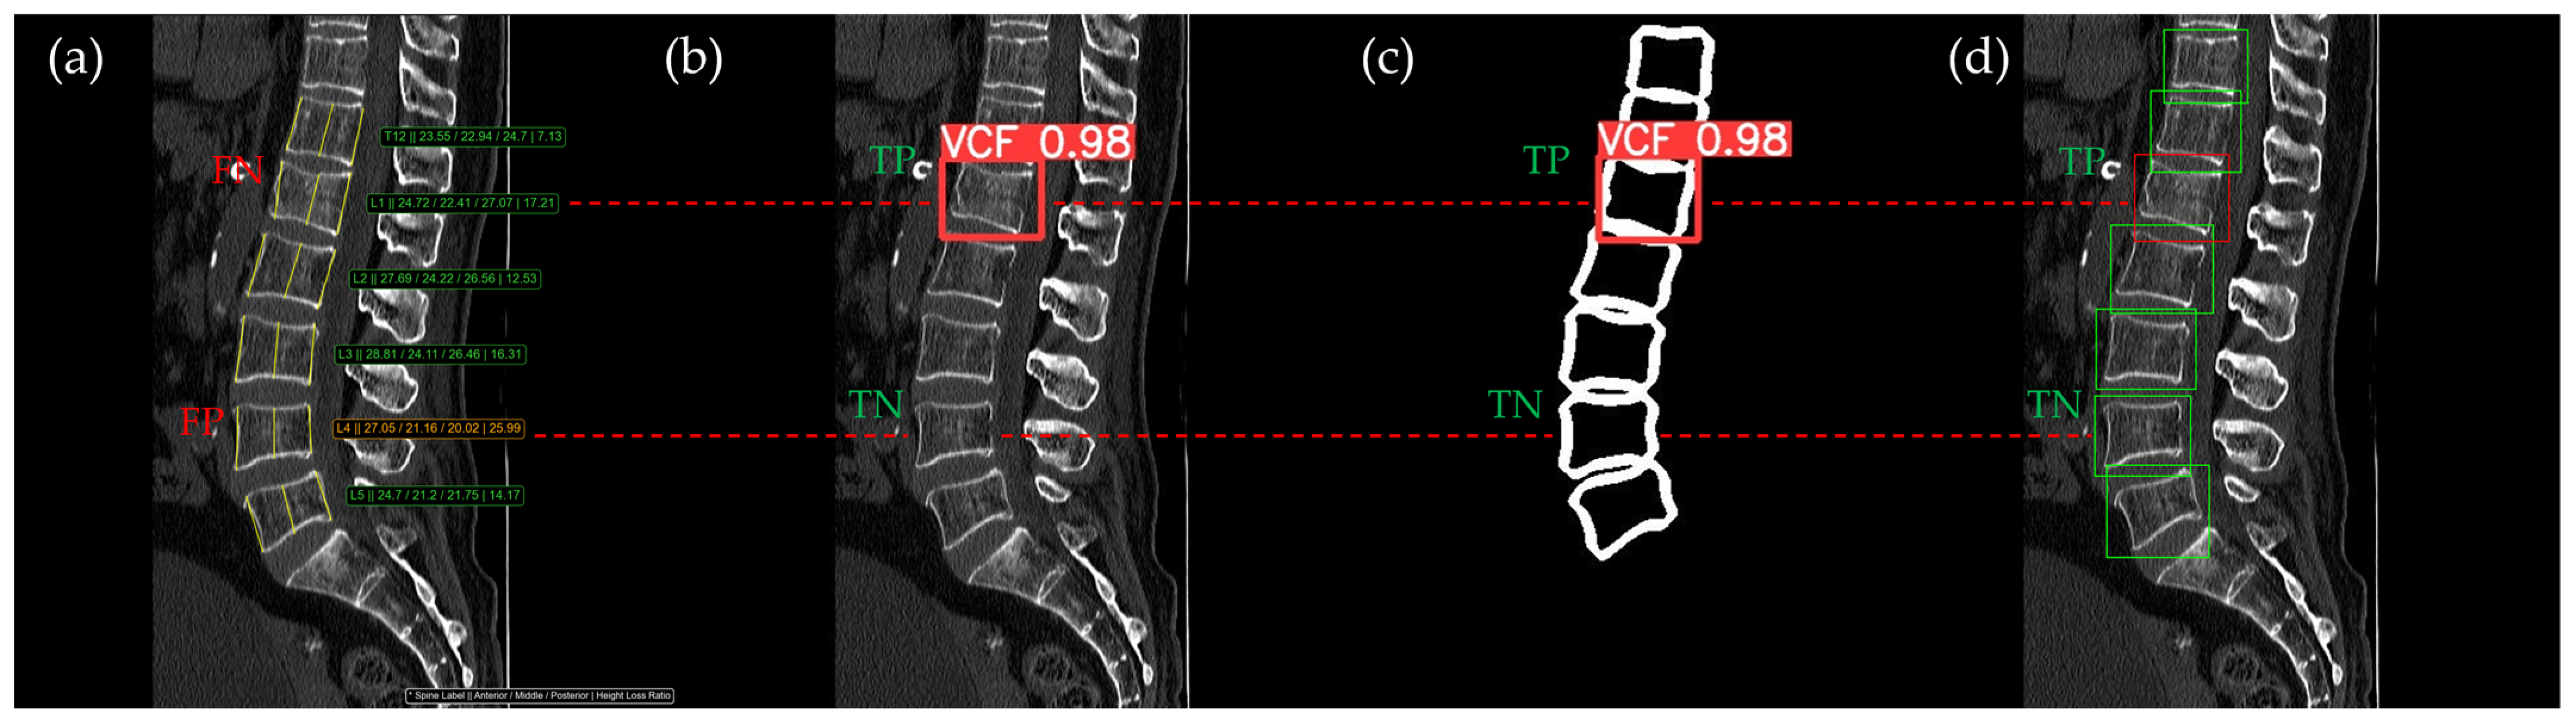

Figure 10, Figure 11, Figure 12, Figure 13 and Figure 14 illustrate typical examples of results for HLR, EEVD, TSVD_SD, and TSVD_DC in patients with acute VCFs. The results of applying different methodologies to the same patient image and identical slice locations were as follows. In the HLR results, each vertebra was marked with yellow solid lines indicating the height measurement lines for the anterior, middle, and posterior regions. The measured height values and HLR percentages were displayed on the right side of the image. If the HLR percentage ranged between 25% and 40%, it was highlighted in orange, while values of 40% or higher were highlighted in red. In the EEVD results, the VCF detection outputs were displayed along with their respective confidence scores based on the input patient images. For the TSVD_SD results, after performing spine segmentation, the model extracted only the spine contour, and the VCF detection results with their corresponding confidence scores were presented. In the TSVD_DC results, bounding boxes were generated for each vertebral body, with normal vertebrae represented in green and vertebrae identified as VCFs displayed in red.

In Figure 10, the acute VCF was present only at the L2 level, characterized by morphological features of an anterior cortical step-off. With the HLR method, the result was an FN, whereas EEVD, TSVD_SD, and TSVD_DC correctly identified it as a TP.

Figure 10. The VCF detection results from four different methods. (a) HLR, (b) EEVD, (c) TSVD_SD, and (d) TSVD_DC. The acute VCF, as confirmed by the radiologist, was located at the L2 level. Both the FN and TP were marked at the same level with a red dotted line.